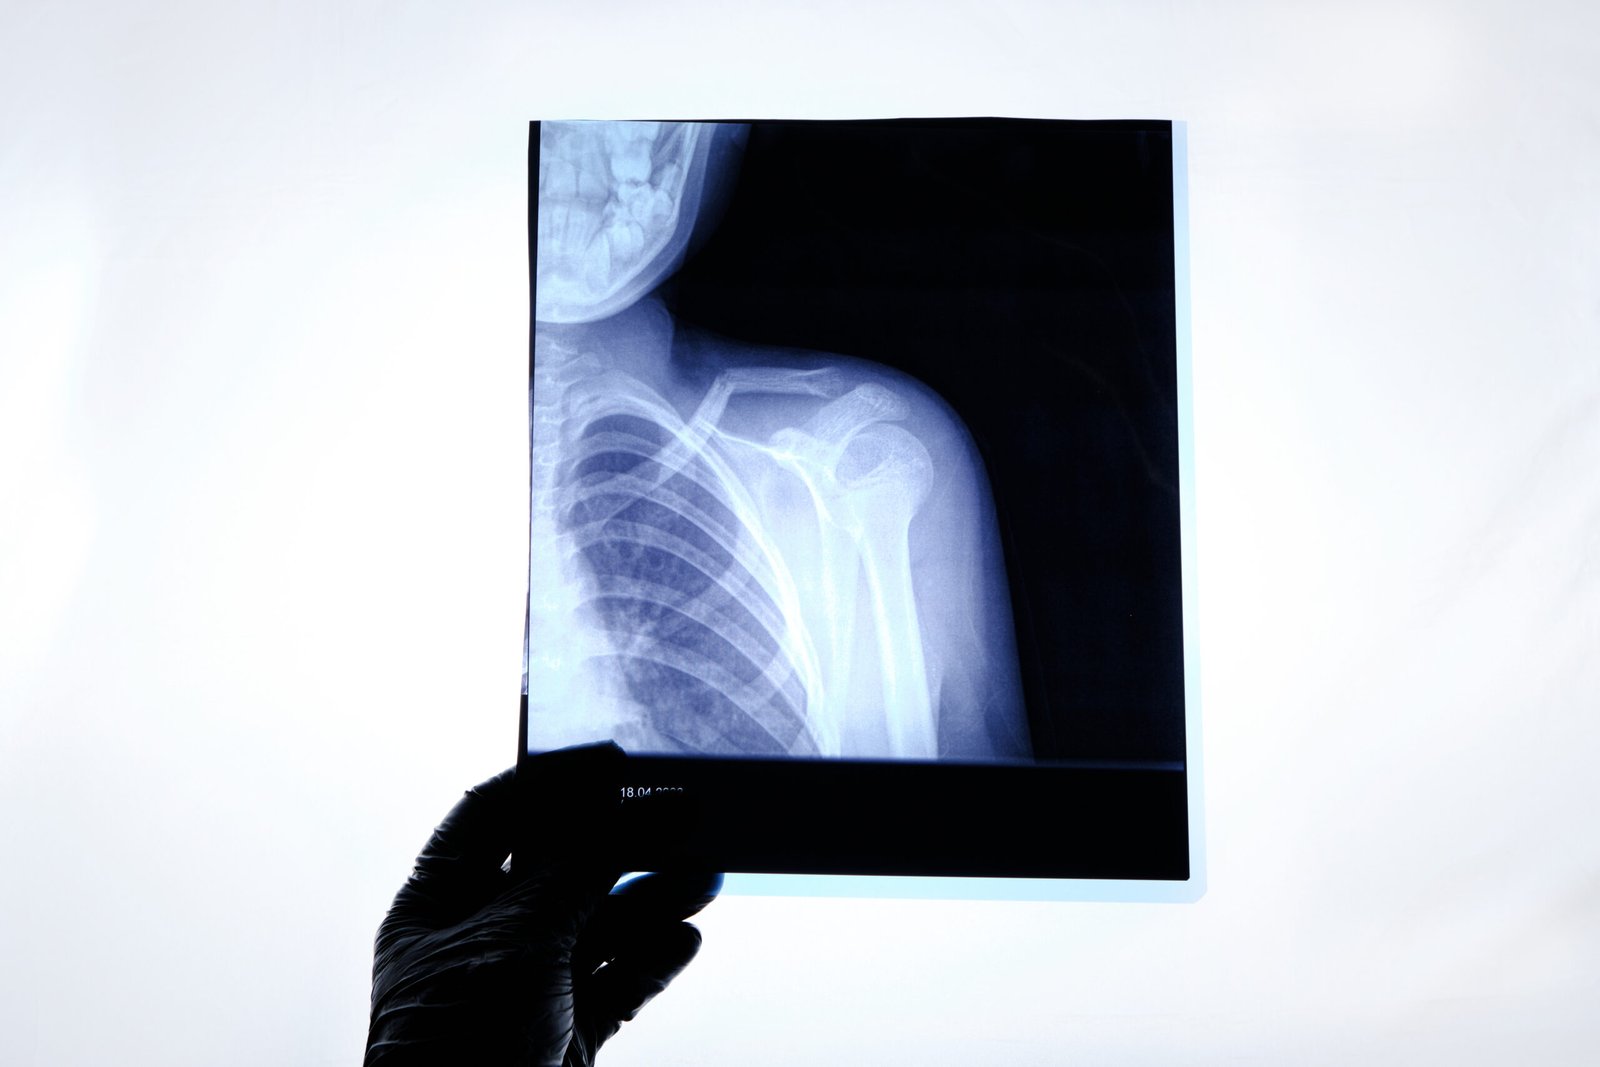

Understanding Shoulder Anatomy

The shoulder is a dynamic and highly mobile complex joint that performs a great array of movements. It comprises: Glenohumeral joint: The rounded articulation type present between the humerus head and the glenoid cavity. Acromioclavicular (AC) joint: A connection between the clavicle and the scapula. Scapulothoracic joint: The moving point of contact between the scapula and the rib cage. The supporting muscles in the shoulder are: Rotator cuff (Supraspinatus, infraspinatus, teres minor, subscapularis). Deltoid, biceps, and triceps for active movements. Tendons and ligaments provide extra strength and promote movement. Understanding the anatomy of the shoulder can help in diagnosing and treating shoulder pain and enhance quality of life.

Diagnosis of Shoulder Pain